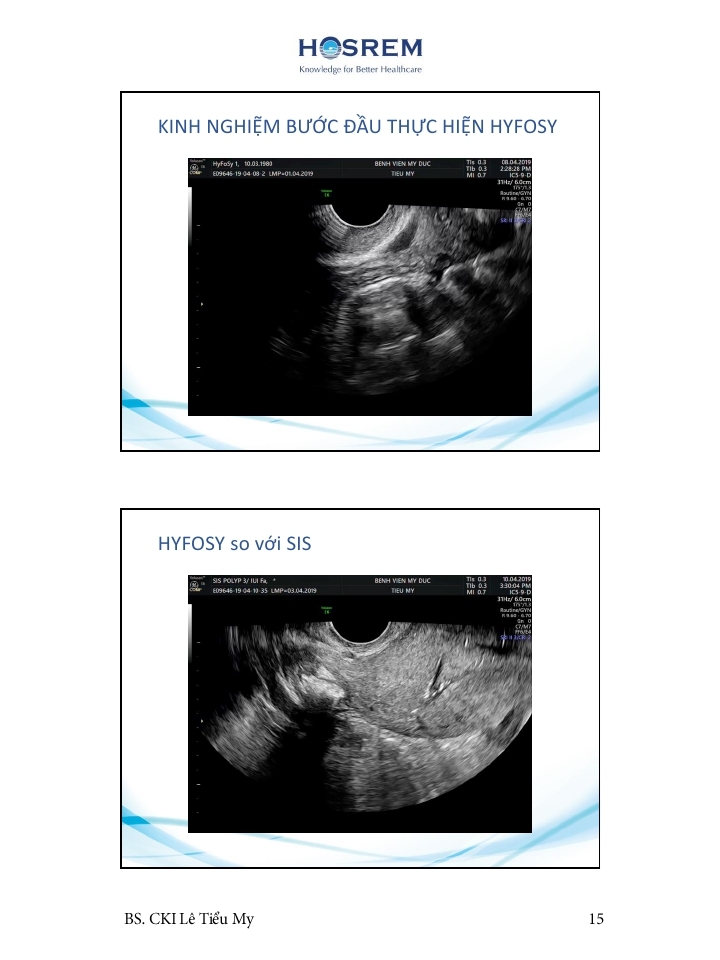

Các phương pháp đánh giá ống dẫn trứng